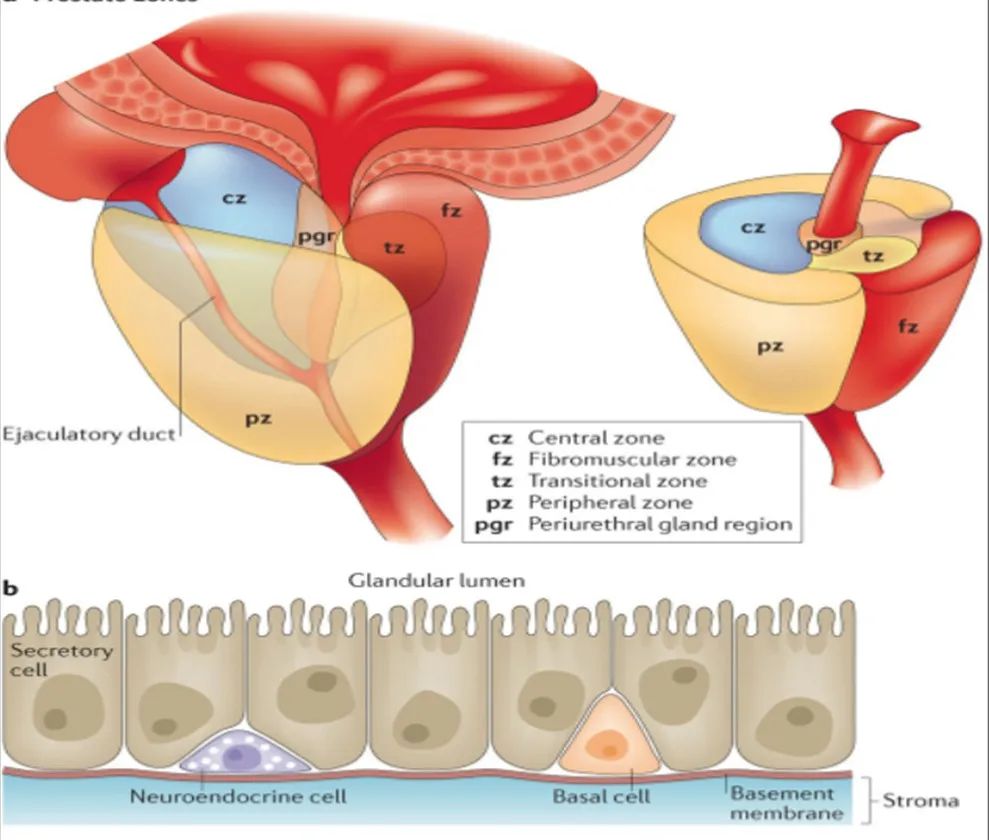

前列腺分区解剖学

70-75% 的前列腺癌起源于外周带 (PZ)。该区域的后部可以通过直肠指检进行检查。

25% 的前列腺癌起源于移行带 (TZ)。极少数前列腺癌出现在中央带或前纤维肌基质中。